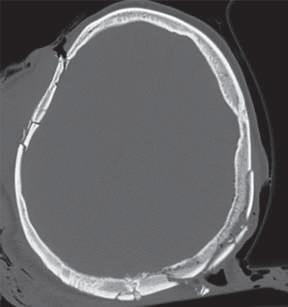

Lesões Ósseas

Palavras-chave: fraturas ósseas.

Keywords: bone fractures.

Introdução

O esqueleto do corpo humano é constituído por 206 ossos que são responsáveis pelas mais diversas funções, nomea damente: proteção dos órgãos internos, suporte mecânico, regulação da homeostasia mineral, funções hematopoiéti cas. Ao contrário dos outros tecidos no corpo humano que após lesão regeneram com tecido cicatricial, o tecido ósseo regenera com osso novo, indistinguível do osso original.

Devido à sua elevada área de exposição, o esqueleto apre senta, frequentemente, sinais de traumatismos, advindo daí a sua importância numa perspectiva médico-legal, quer em termos de patologia, quer de clínica forense. Após uma le são óssea, há a formação de um hematoma e uma resposta inflamatória que vai induzir a formação de osso novo por osteoblastos locais. Há a constituição de uma matriz co lagenosa e a diferenciação de células mesenquimatosas, com a formação de cartilagem. Os condrócitos proliferam, hipertrofiam e segregam fatores que vão induzir a ossifi cação da cartilagem, com a conversão de cartilagem em osso novo – ossificação endocondral. Este osso é remode lado pela ação combinada de osteoblastos e osteoclastos, dando origem a osso maduro de acordo com as linhas de stress/tensão (Clohisy et al., 2009). Dependendo do timing da lesão óssea, assim, poderemos ter lesões ante mortem, peri mortem e post mortem.

A presença de um calo ósseo, denotando assim um osso que teve tempo para maturar, aponta para uma lesão ante mortem. Já uma lesão que não apresenta sinais de conso lidação pode ter tido origem peri mortem ou post mortem A constituição do osso é alterada após a morte, com perda de água e da sua elasticidade, tornando assim o osso mais quebradiço, o que vai influenciar as características das lesões ósseas post mortem

Nas lesões peri mortem, encontra-se uma coloração mais uniforme e a presença de fraturas incompletas, em espiral e de tensão-compressão, frequentemente mais oblíquas. Nas lesões post mortem, em que o osso se encontra mais seco por desidratação, a coloração pode ser mais heterogénea

(por exposição ao meio envolvente), as superfícies de fratu ra vão apresentar-se mais regulares, com bordos retos, e as fraturas serão mais longitudinais e transversais irregulares (Cunha & Pinheiro, 2005/2006).

A forma e a aparência das lesões ósseas podem refletir não só a direção, a área, a velocidade, a massa e a forma do objeto produtor da lesão, mas também as próprias ca racterísticas inatas do tecido ósseo, como o seu conteú do mineral, as características físicas do osso em questão ou eventuais alterações patológicas do mesmo (Cunha & Pinheiro, 2005/2006). Sendo uma combinação de matéria orgânica e inorgânica, o tecido ósseo é capaz de sofrer de formação elástica e plástica antes da falência. Mas uma vez iniciada a fratura, esta propagar-se-á através do osso até que a energia seja dissipada.

Existem três tipos principais de lesões: cortantes, contun dentes e perfurantes. Quando há uma combinação destas, podemos ter lesões mistas, como as perfuro-contundentes provocadas por projéteis de armas de fogo. Por regra, os diferentes tipos de lesões apresentam características típi cas dos instrumentos responsáveis pelas mesmas, apesar de o mesmo instrumento poder ser responsável por diferen tes tipos de lesões e a mesma lesão poder ser provocada por instrumentos diferentes.

36.1

Lesões cortantes e corto-contundentes

As lesões provocadas por instrumentos cortantes vão de pender das características da sua lâmina, o que pode per mitir identificar o instrumento responsável pelas mesmas. É possível a análise da impressão provocada no osso – dos entalhes ósseos e dos seus bordos, paredes e pavimen tos – e identificar padrões nas estrias que permitam dis tinguir o tipo de instrumento. A análise das estrias através da microscopia eletrónica permite identificar imperfeições específicas das lâminas, o que pode levar à identificação do instrumento específico responsável por uma determi nada lesão. A partir da análise das lesões, pode ser ainda

© PACTOR 473

36

possível identificar a direção do movimento e os padrões de corte (Bartelink et al., 2001; Ciallella et al., 2002; Saville et al., 2007; Symes, 1992; Symes et al., 2001).

Assim, podemos encontrar lesões produzidas por instru mentos de gume liso, serrilhado ou complexo, simples ou duplo. Quando além da ação do gume o instrumento apre senta um peso elevado, vamos ter lesões de características mistas (corto-contundentes), como acontece com lesões

provocadas por machados, espadas ou catanas (Figura 36.1), que atuam pela ação do peso e do gume cortante (Humphrey & Hutchinson, 2001; Lewis, 2008).

As lesões ósseas do tipo cortante ou corto-contundente ocorrem em grande número no contexto de acidentes de trabalho com trauma dos membros superiores, nomeada mente das mãos (Figura 36.2).

Fig. 36.1 Lesão por catana

Fig. 36.2 Lesão por serra